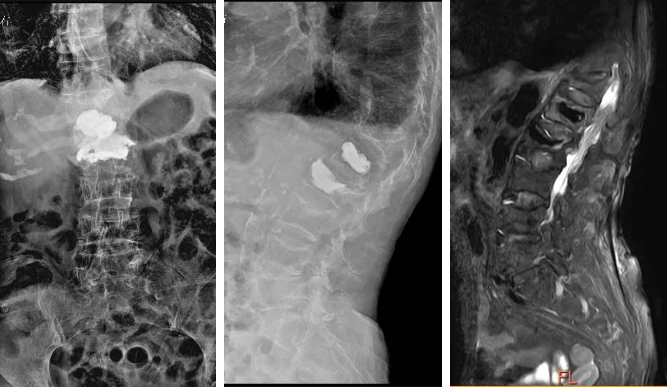

住院后,李永革主任医师团队立即对张奶奶进行了详细的体格检查,发现在胸腰段区域有压痛和叩击痛,于是复查了X线及磁共振。

X线显示张奶奶多个节段的椎体都有不同程度的压缩骨折,其中胸12椎体压缩极为严重,腰1、腰2椎体有进行过经皮穿刺骨水泥成形术的征象,而磁共振检查结果显示,胸12椎体压缩骨折有偏新鲜的影像信号,这与张奶奶自己描述的疼痛位置和李永革主任医师团队体格检查的结果是相符的,所以李永革主任医师考虑患者再次发生了胸12椎体压缩骨折,才导致目前严重的疼痛。

入院后复查的X线片和磁共振